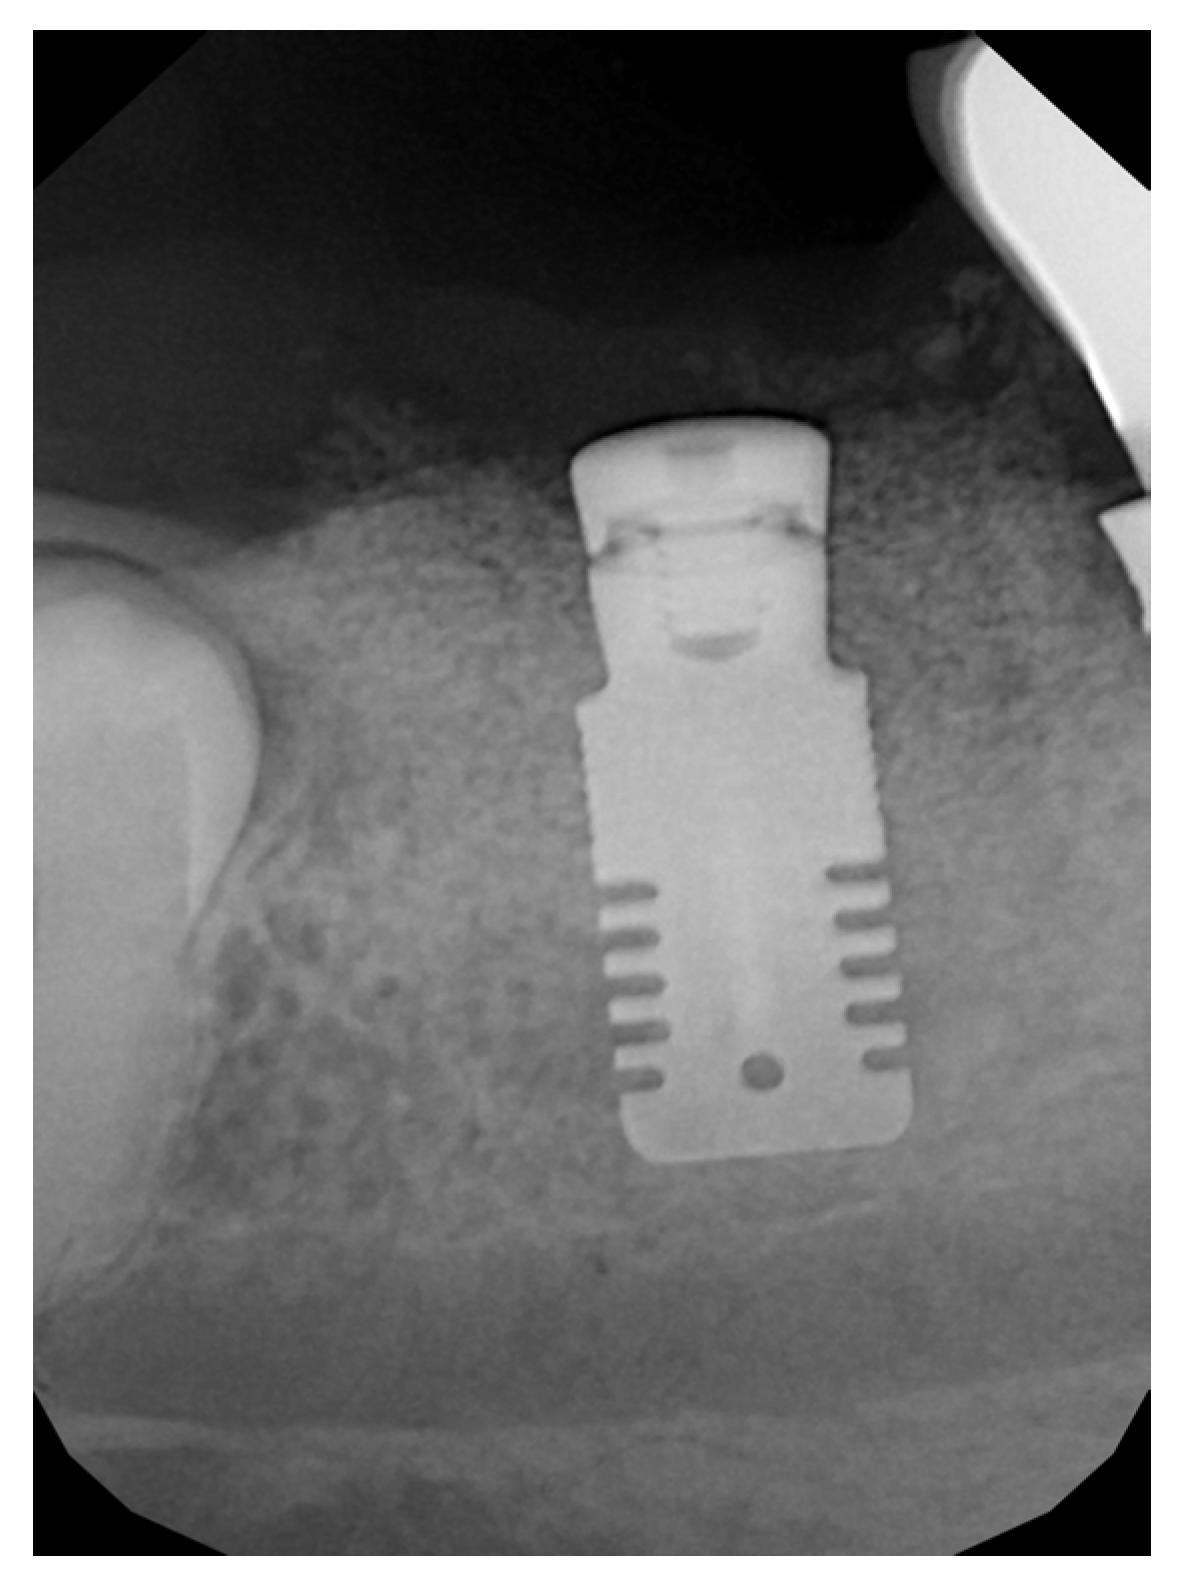

2.2. Surgical Technique